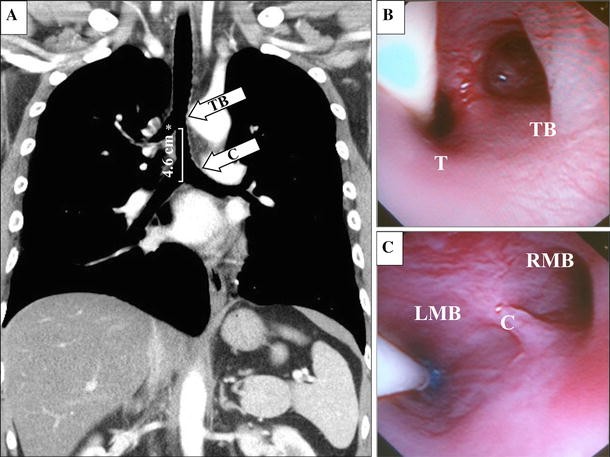

A) A preoperative computed tomography scan of the patient’s chest revealed a tracheal bronchus (TB; asterisk) of the right upper lobe originating from the middle of the trachea (T) 4.6 cm above the carina. The labelled upper and lower white arrows correspond to the fibreoptic bronchoscopic (FOB) views at the level of the tracheal bronchus bifurcation and the carina (C), respectively. B) The FOB view of the tracheal bronchus bifurcation that appears to mimic the appearance of a normal carinal bifurcation. C) The FOB view showing the carina, right mainstem bronchus (RMB), and the properly positioned endobronchial blocker in the left mainstem bronchus (LMB)

After applying standard monitoring,5 general anesthesia was induced with intravenous propofol. Neuromuscular blockade was achieved with rocuronium, and anesthesia was maintained with a continuous infusion of remifentanil and sevoflurane 1-3vol% in 50% air/oxygen. The patient’s trachea was intubated with a Mallinckrodt™ single-lumen ETT (Covidien Inc., Mansfield, MA, USA) with an 8.0-mm internal diameter. Fibreoptic bronchoscopy revealed that the take-off of the tracheal bronchus mimicked the appearance of the normal carinal bifurcation (Figure B). The trachea was divided into the tracheal bronchus and the main trachea, forming a sharp ridge at the junction where they diverged. As the FOB advanced further into the main trachea, the patient’s actual tracheal carina was visualized (Figure C). Compared with a normal carinal appearance, our patient’s carina showed an atypical appearance with a laterally shifted main bronchi forming an obtuse angle of divergence with a blunted carinal ridge.